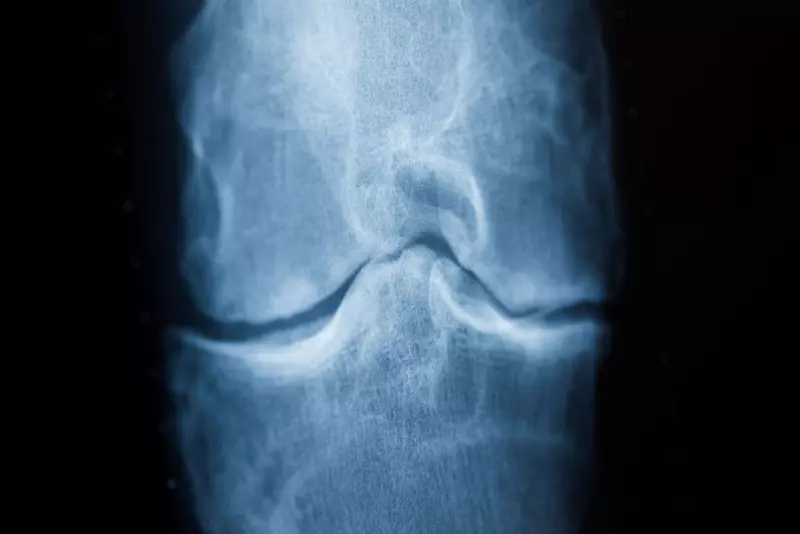

Die Resultate deuten darauf hin, dass bei den Probanden, die ihre Fußstellung korrigierten, der Abbau des Knorpels an der Innenseite des Knies verlangsamt wurde. «Obwohl unsere Ergebnisse in zukünftigen Studien bestätigt werden müssen, legen sie die Möglichkeit nahe, dass die neue, nichtinvasive Behandlung dazu beitragen könnte, eine Operation hinauszuzögern», wird Mazzoli laut Mitteilung zitiert.

Außerdem reduzierte sich den Probandenangaben zufolge der Schmerz auf einer Zehn-Punkte-Skala um 2,5 Punkte. Laut Mitteilung ist das ein «Effekt, der dem von rezeptfreien Schmerzmitteln entspricht».

«Diese Ergebnisse unterstreichen, wie wichtig eine personalisierte Behandlung statt eines Einheitsansatzes bei Arthrose ist», erläuterte Co-Studienleiterin Mazzoli. «Diese Strategie mag zwar schwierig klingen, doch dank der jüngsten Fortschritte bei der Erkennung der Bewegung verschiedener Körperteile mit Hilfe künstlicher Intelligenz könnte sie einfacher und schneller als je zuvor werden.»